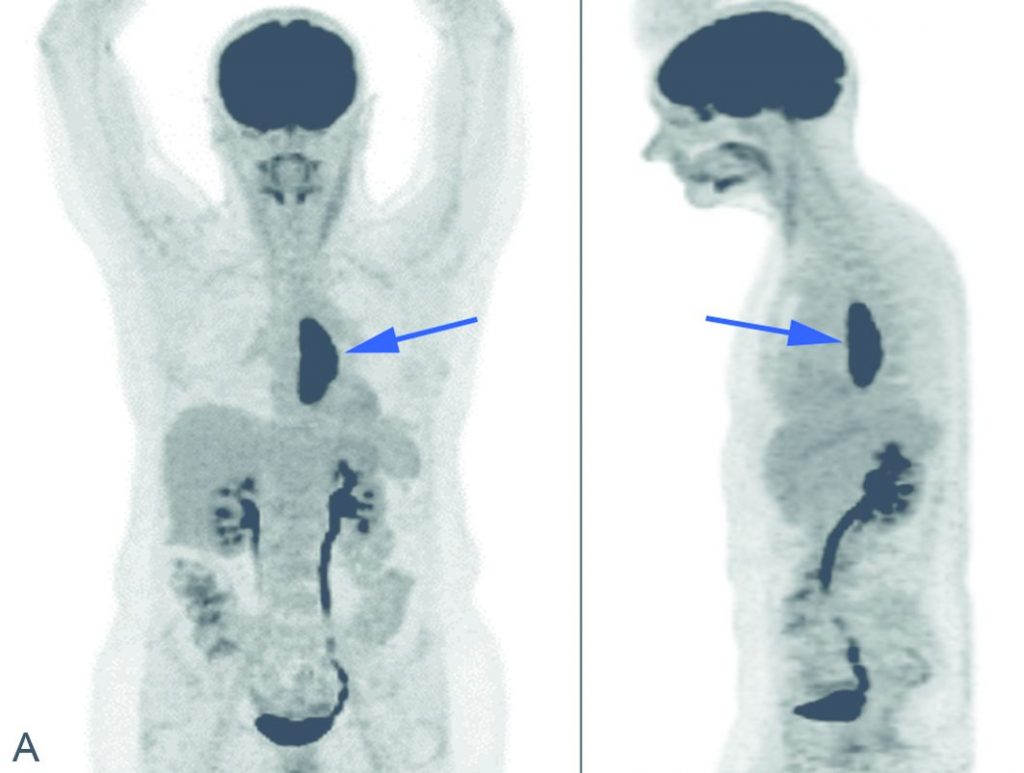

La TEP-TDM au 18FDG est recommandée dans le cadre du bilan d’extension préthérapeutique avant radiochimiothérapie ou avant chirurgie (figure 17.2) ; l’examen peut être proposé :

- pour la planification de la radiothérapie ;

ou pour l’évaluation de la réponse à la radiochimiothérapie ou à la chimiothérapie néoadjuvante, et peut être proposé pour la planification de la radiothérapie ou en cas de suspicion de récidive du cancer.

Fig. 17.2. Images TEP au 18FDG (A) et TEP au 18FDG fusionnée à la TDM (B) en coupes axiales réalisées dans le cadre du bilan d’extension d’une tumeur du tiers inférieur de l’œsophage (flèche) montrant une hyperfixation (tête de flèche) en regard d’un nœud lymphatique cœliaque.

Source : CERF, CNEBMN, 2022.

La tumeur apparaît au scanner comme une sténose œsophagienne. La paroi de l’œsophage est épaissie, souvent de façon asymétrique, circonférentielle ou non (cf. figure 17.1). En TEP-TDM au 18FDG, elle est fortement hypermétabolique. On apprécie la hauteur de la tumeur et sa localisation précise surtout grace à la TEP (cf. figure 17.2), et son extension aux organes de voisinage surtout grâce au scanner dont la résolution spatiale est plus élevée que la TEP. L’importance de la dilatation d’amont est le reflet de la sévérité de la sténose.